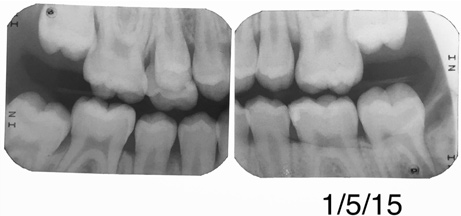

Fig 2.  Circumferential gumline decalcification (Fig 1) and bitewing (Fig 2) of a 28-year-old woman.

Figure 2

A 28-year-old woman, who previously had braces, had circumferential gumline decalcification (Figure 1) and wished to arrest lesions before they worsened (bitewing, Figure 2). The following protocol is consistent with the product instructions for the resin infiltration material from DMG America, which is the only commercially available resin infiltration system in the US.